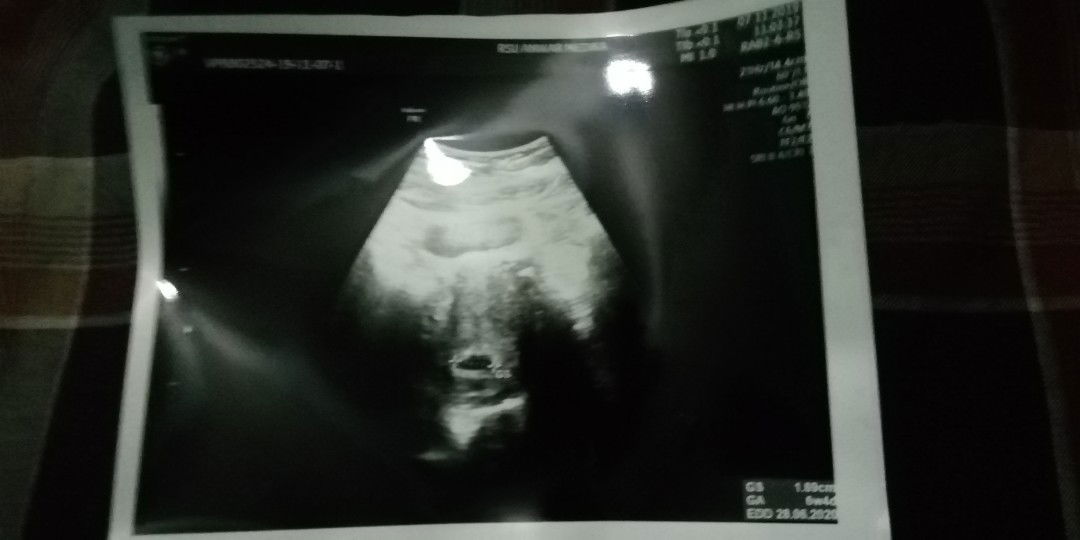

Bun mau tanya donk yang bner untuk usia kehamilan itu yang menurut hasil usg apa yang menurut HPHT ya saya koq jadi bingung ya kalau menurut HPHT saya sudah usia kandungan 10 minggu tapi kemari waktu usg koq masi 6 minggu ya itu pun ke 2x usg tpi hsil ttep sama usia 6 minggu pdhal kalau menurut HPHT yang waktu usia kehamilan 8 minggu usg krna ada pendarahn waktu di usg masi 6 minggu 5 hari itu usg yang transviganal dan waktu kembali usg di usia kehamiln 10 minggu waktu di usg masi juga 6 minggu 2 hari itu usg yang biasa ndka tau apa nama usgnya yang di tempelkan ke perut ? yang bner itu yang mana yang bun saya jadi binghung dan takut krna liat hsil usg usia masi segitu* aja.

Mohon doanya ya bun semoga janinnya tidak ada kendala. Sedih ketika dokter bilang kalau kantong janinnya tidak berkembang dengan sempurna ??hanya kesedihan yang saya rasakan kehamiln ke dua juga ada maslh bru usg karna ada pendrahan sempet di kasi obat pnguat alhamdulilah sudah berhenti dan waktu di usg dokter bilang kalau kntongnya tidak terbentuk dengan sempurna dan perkembngan janinnya juga lambat harusnya udah usia 8 minggu tapi waktu di usg masi 6 minggu ??? minta doanya ya bun semoga baik* saj dan bisa kembali normal lagi ??